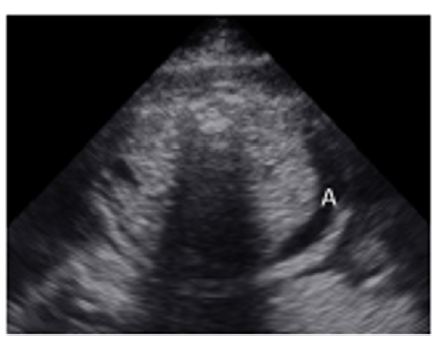

A 35-year-old pregnant woman being in the 29th Gestational Week (GW) was admitted to the Department of Obstetrics and Gynecology of University of Szeged, due to fetal tachycardia with a Fetal Heart Rate (FHR) of 250/min. The mother suffered from hypertension before the pregnancy and underwent calcium channel blocker therapy (Verapamil), which was replaced with methyldopa (Dopegyt) during the pregnancy. Nuchal translucency and biomarkers measured in the first trimester were normal. There was no positive family history for Congenital Heart Defect (CHD). A fetal echocardiography was performed, according to the AIUM guidelines [1]. The FHR was between 240-260/min, the Atrio-Ventricular (AV) conduction was 1:1, a Supraventricular Tachycardia (SVT) was diagnosed (Figure 1). Fetal echocardiography revealed an abnormal four-chamber view, a very large right atrium and a very small right ventricle, the tricuspid valve was abnormal, attached deeply in the right ventricle and the apical displacement of the valve led to the atrialization of the right ventricle and a holosystolic tricuspid regurgitation could be detected by Doppler. The pulmonary artery was very narrow, the diameter of the aorta was twice as big as the diameter of the pulmonary artery, therefore a duct-dependent CHD with decreased pulmonary circulation was suspected. The abnormal anatomy of the fetal heart was characteristic for Ebstein anomaly (Figure 2), which is a complex cyanotic CHD. Pericardial or pleural effusion was not observed, but some ascites was already seen in the abdominal cavity (Figure 3), indicative of incipient fetal heart failure.

Figure 3:Transversal abdominal view of the 29 GW old fetus: abdominal fluid, ascites can be seen in the fetal abdomonal cavity (A=ascites).